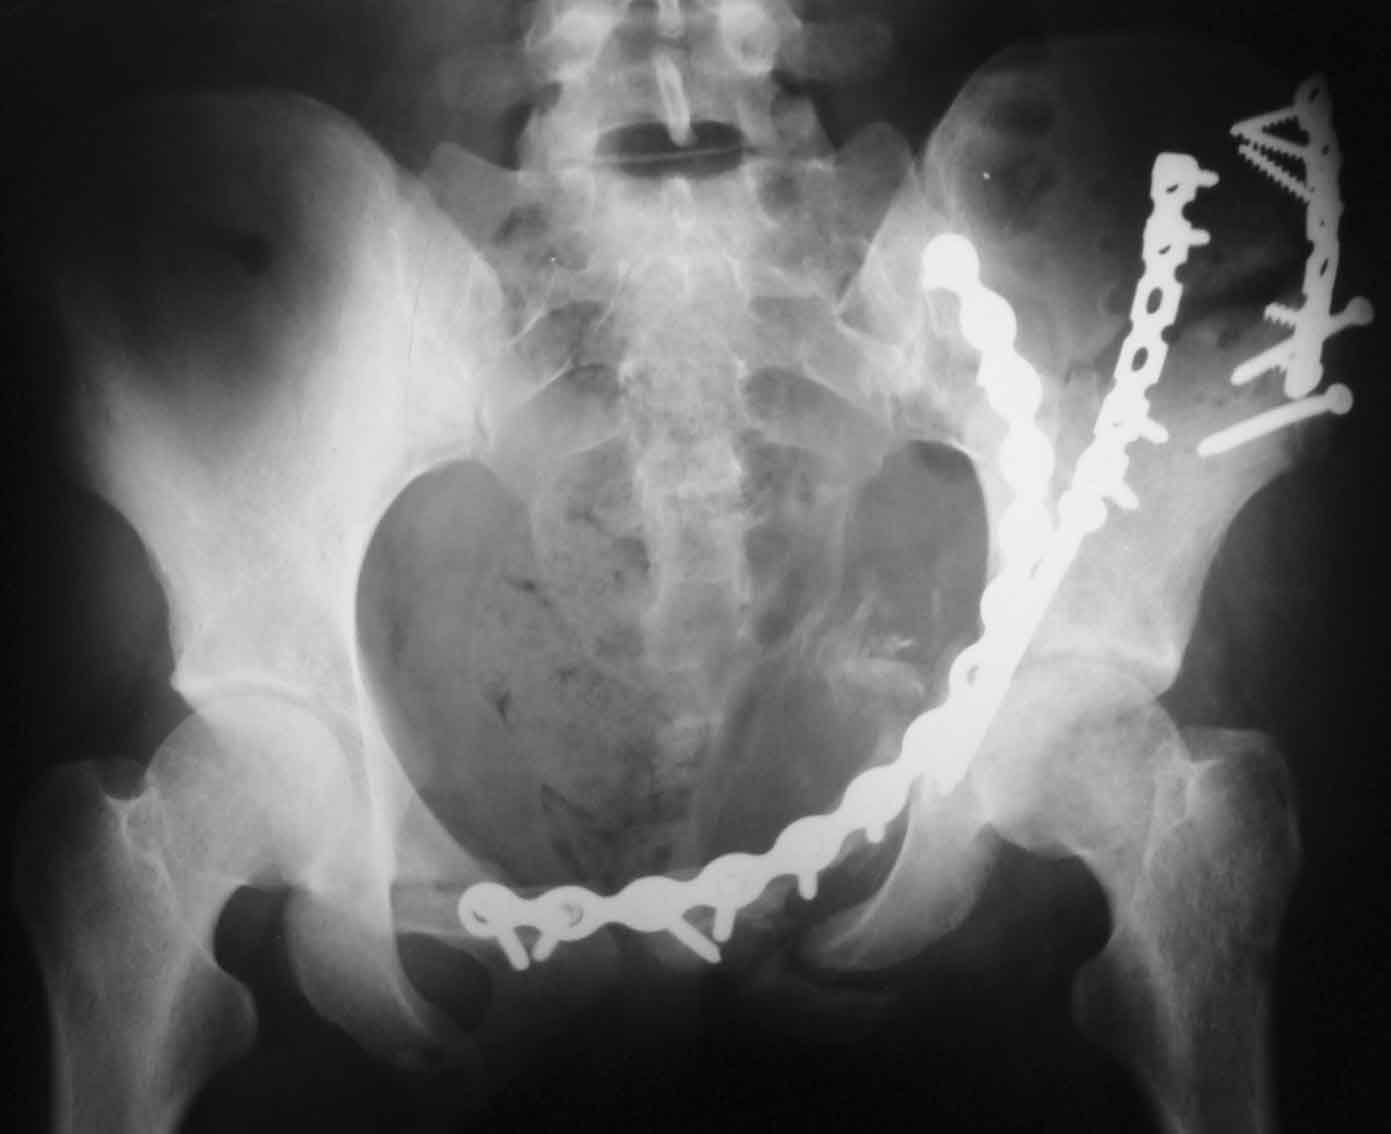

Рентгенограмма после операции. Изв. за качество. На днях переделаем.

Рентгенограммы после операции

Прямая проекция

inlet

подвздошная

запирательная